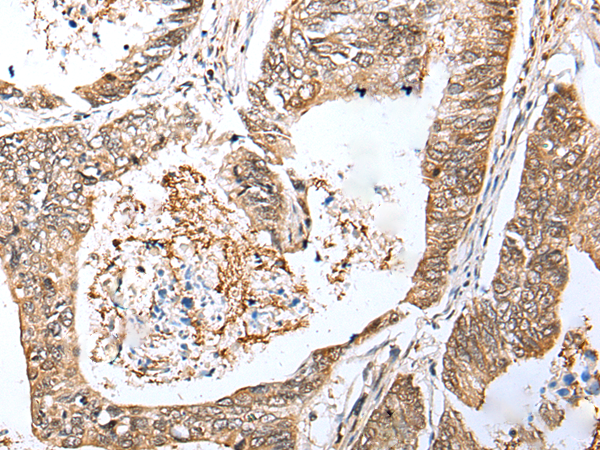

LRRC19 is a member of the extracellular leucine-rich repeat superfamily, a family of proteins that are thought to have diverse functions such as cell adhesion, signaling, and innate immunity. LRRC19 is closely related to the Toll-like receptors (TLRs), especially TLR3. LRRC19 does not contain a cytoplasmic Toll/IL-1 receptor (TIR) domain, but can activate NF-kappaB and induce the production of proinflammatory cytokines after stimulation with the TLR3 and other TLR ligands, suggesting that LRRC19 may play a role in the recognition and the response to certain pathogenic microorganisms. LRRC19 has also been suggested to be a potential biomarker for pancreatic tumor sensitivity to the anti-cancer, small molecule Src inhibitor AZD0530.

ELISA, WB, IHC

IHC positive control:

IHC Recommend dilution: